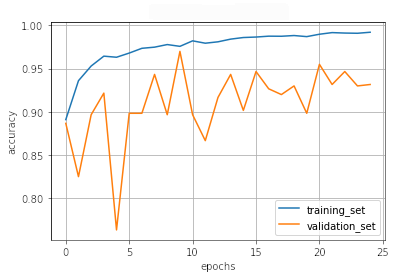

III.2 Classification results

The training procedure in all scenarios has converged. Looking at the evolution of training and validation accuracy (Fig. 11a) indicates that a larger validation dataset would be beneficial. To stabilise the classifier training a procedure of multiple training runs to select the best model is used (Materials and methods). Resulting classifiers are able to discriminate between classes with good precision, for example, see the confusion matrix of the best overall model presented in Fig. 11b. It can also be seen that for the normal class, the rate of misclassified images as COVID-19 ones is higher than for other classes. This effect is present for all models although smaller for the ones based on the EfficientNet-B0 architecture. In addition, the EfficientNet-B0 variants excel if the correct classification of viral pneumonia class images with the smallest rate of errors. However, the EfficientNet-B0 GAN augmentation scenario shows increased misclassification of healthy images which leads to a poor performance. The evolution of the training accuracy as well as confusion matrices for all models are summarised at the end of this section.

Training results for the two architectures are summarised in Figs. 13, 14, 15, 16, and Table 3. For each architecture four scenarios are considered as described in Training process part of the Materials and methods Section.